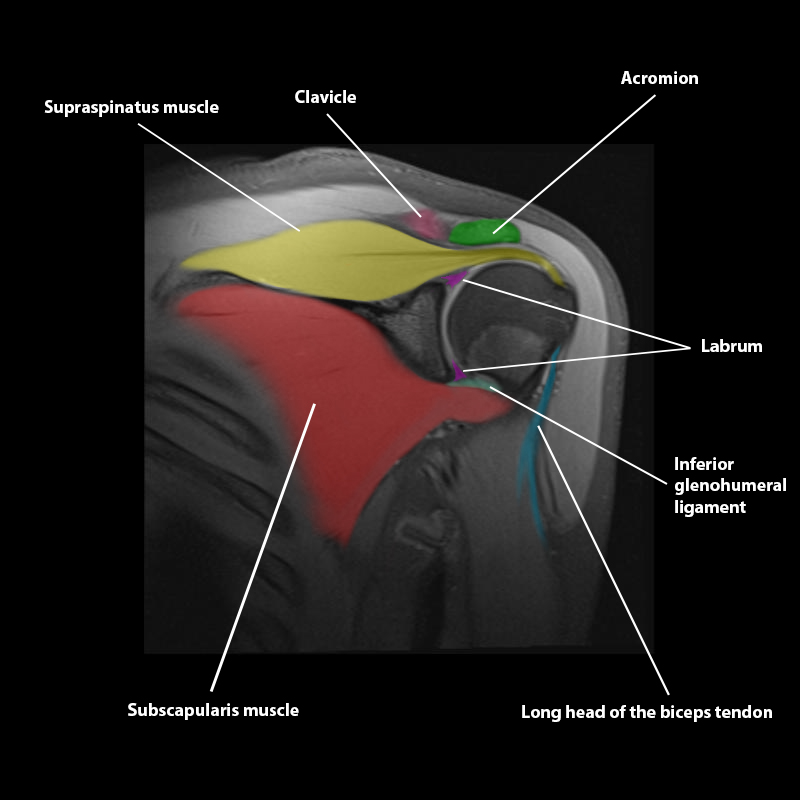

Shoulder MRI Anatomy